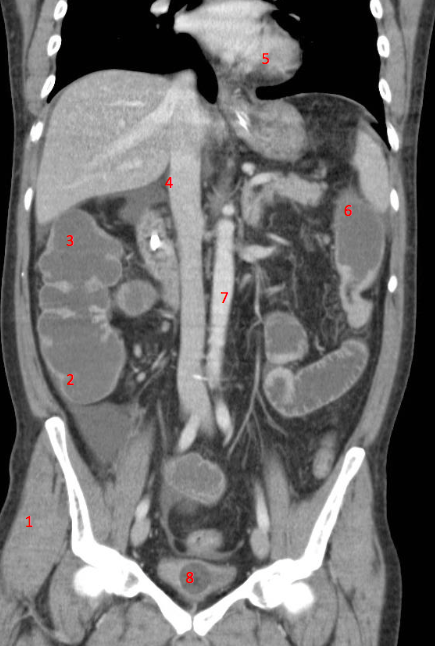

1

Number 3?

IVC

2

Number 1?

R Kidney

3

Q

A

Perfectly

4

Number 2?

How well did you know this?

Not at all

5